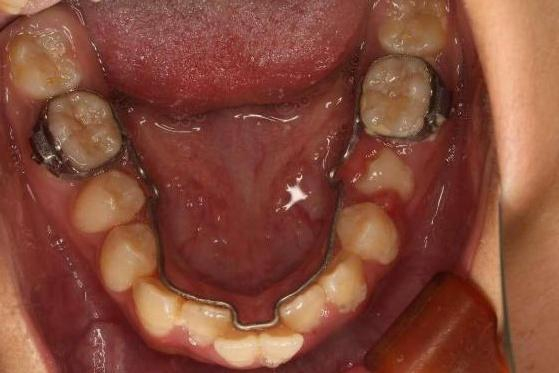

舌弓保持替牙间隙并隐形矫正排齐牙齿。